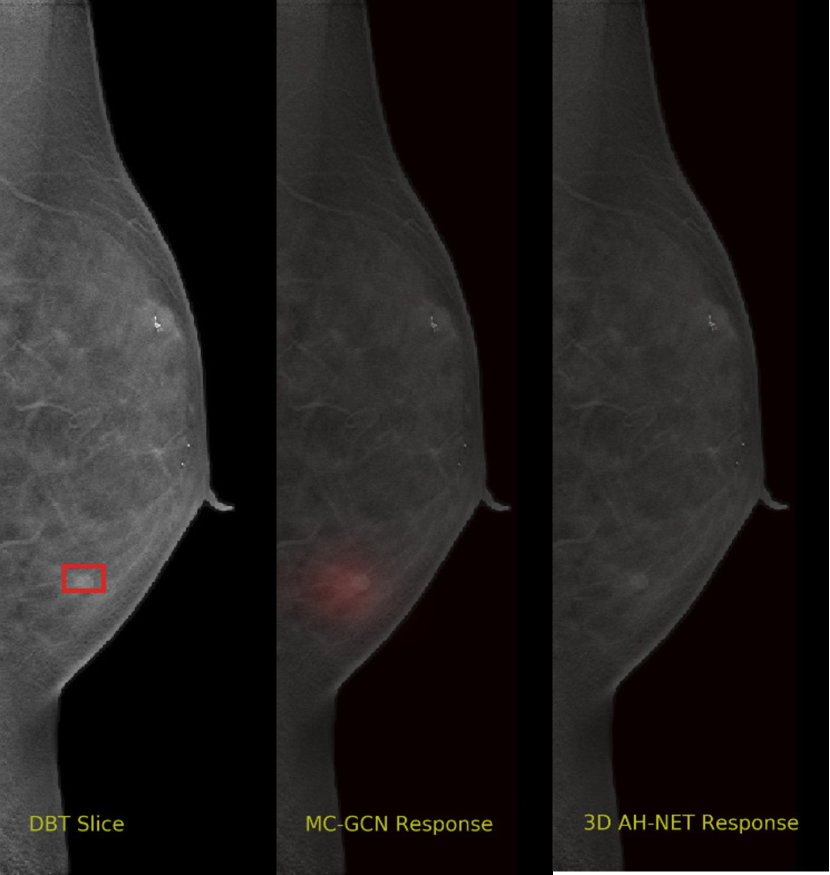

Appendix A Visual Cases of the DBT dataset

We selected some example slices from the DBT dataset to demonstrate the advantage of our proposed AH-Net for the Breast cancer screening. From Fig. 8 to Fig. 12, we show slices from five test DBT volumes that both the MC-GCN and the proposed 3D AH-Net could successfully detect the suspected breast lesion. The original DBT slice is shown on the left with the lesion annotated by our radiologist. Please note the original annotation is a 3D box. The figures in the middle and on the right are response maps from MC-GCN and 3D AH-Net overlaid on the original image, respectively. The detection locations obtained with non-maximal suppression are displayed with cross markers. As shown in the images, the proposed network can detect breast lesions varying in sizes and appearances. The confidence of the 3D AH-Net is usually higher than that of MC-GCN. From Fig. 13 to Fig. 17, we show five volumes that MC-GCN failed to detect the lesions since the lesions were not distinguishable from other breast tissues using the information within the slice. In contrast, 3D AH-Net was able to detect the lesions from such volumes using the 3D context between slices. As shown in Fig. 18 to Fig. 22, there are also volumes with lesions that both network failed to detect. Such lesions normally reside in the dense breast tissues. The boundary between these lesions and the normal breast tissues usually have low contrast. The networks sometimes also confuse them with other roundish structures in the breast such as lymph nodes or skin moles.

Refer to caption

Figure 13: Example DBT slice 6 with a lesion that can only be detected by 3D AH-Net. The lesion is highly blended within the dense breast tissues which makes it challenging for both the radiologists and the networks to detect through a single slice. In contrast, the lesion can be detected by considering the consistency of the structure across a few neighbouring slices.

Figure 14: Example DBT slice 7 with a lesion that can only be detected by 3D AH-Net. The lesion is highly blended within the dense breast tissues which makes it challenging for both the radiologists and the networks to detect through a single slice. In contrast, the lesion can be detected by considering the consistency of the structure across a few neighbouring slices.